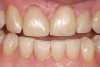

Figure 9  Preoperative photograph of a case requiring significant lengthening. There is at least medium risk of flexure and unfavorable stress, and some of the substrate would be dentin. Thus, Category 1 materials were eliminated as a choice.

Figure 9

Figure 10  Postoperative photograph after Category 2 materials were applied, with minimal porcelain layering in the incisal one third.

Figure 10